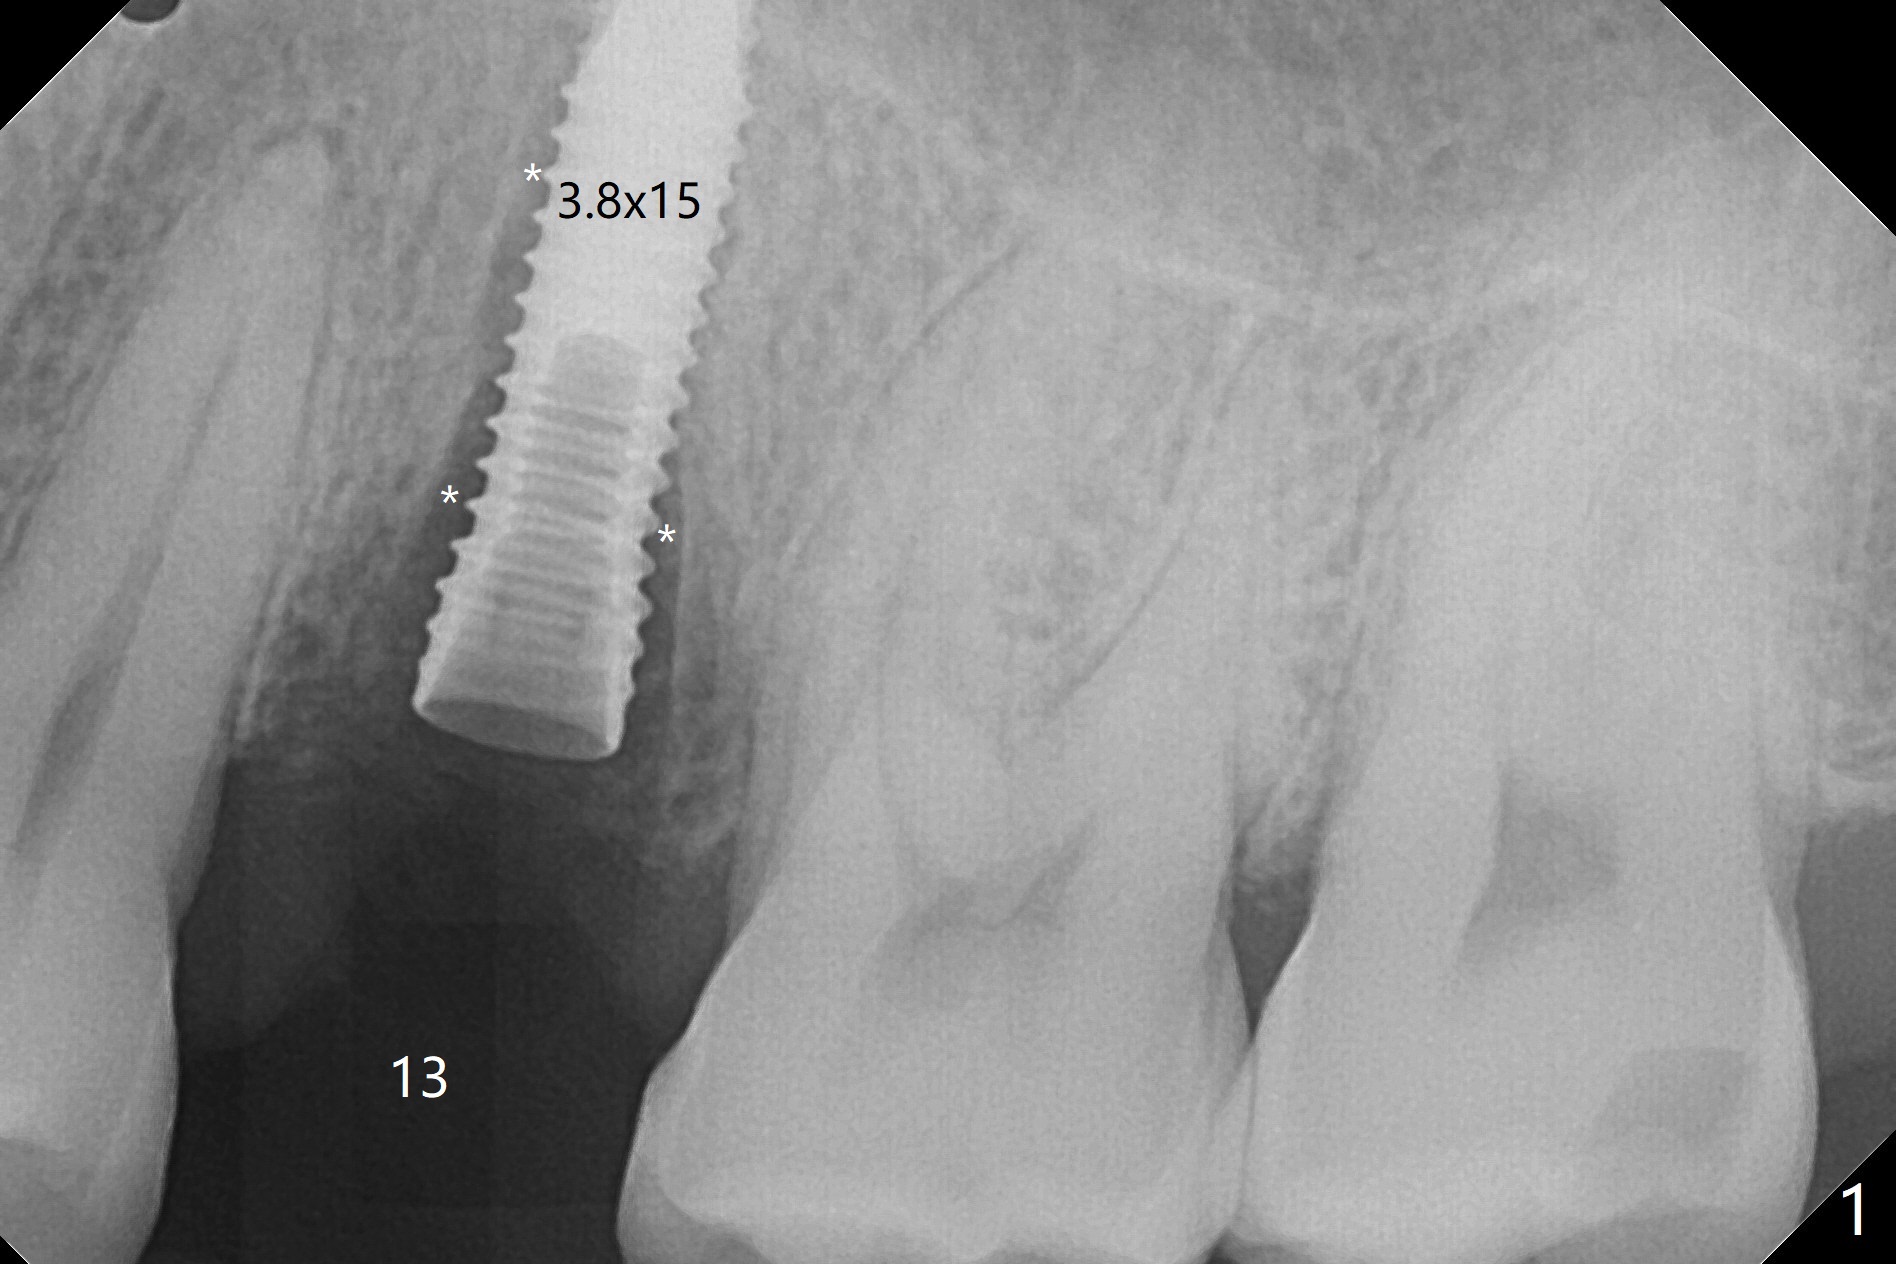

DIO lab refuses fabricating guide because of the large socket and recommends extraction and socket preservation at #13. Due to short apical bone (Fig.5,7), a long dummy implant (3.8x15 mm) is placed with periimplant space immediately post extraction (Fig.1 *). The final implant is larger (4.5x15 mm) with simultaneous sinus lift and periimplant bone graft (Fig.2,6,8 *). To repair the palatal crest defect (Fig.3 *) associated with tooth fracture (Fig.5 white dashed line), the implant is not placed too palatal with sufficient amount of the bone graft (Fig.4,6 *). The native bone (higher in bone density, Fig.9 white arrowheads, as compared to black one (for bone graft)) appears to have grown into the space between implant threads 5.5 months postop. The permanent crown/abutment is loose 1 year 9 months post cementation; after proximal reduction (Fig.10 arrowheads), the abutment is reseated completely. Pick up impression is taken and a healing abutment is placed. A few days later, the crown and abutment (separate) are seated passively; the abutment screw is retightened; the crown is re-cemented. The crown and abutment is removed for residual cement removal (Fig.11). Since there is mild buccal plate atrophy (Fig.11 B), the crown has a buccal lip (Fig.12 B) to prevent food impaction. The lip makes it difficult to remove residual cement intraorally. Therefore an access hole is necessary (Fig.13).